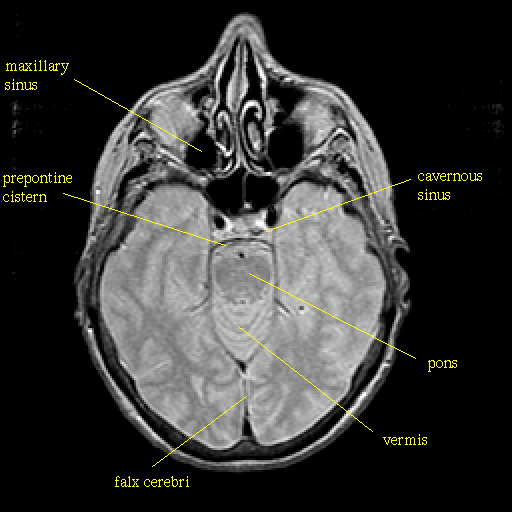

Proton density-weighted structural MR: Slice 19

Slice 19